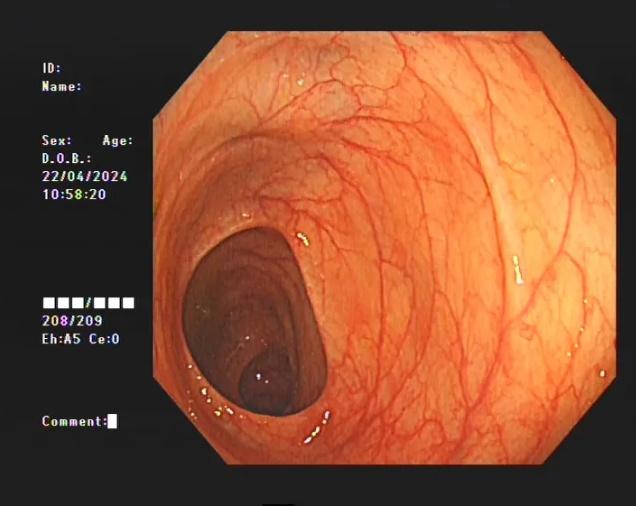

据医生介绍,临床上许多患者自行口服药物后筛查肠镜均有不同程度的结肠黑变病。正常的结肠黏膜就像我们的口腔黏膜一样,是淡红色的,看起来光滑平坦,黏膜表面的小血管纹理清晰可见。而结肠黑变病的肠黏膜色泽呈现棕色、褐色,有豹纹或者蛇皮一样的条状纹,严重的甚至会变成黑色。

正常的肠道。图源:淮安市中医院

正常的肠道

正常的结肠黏膜就像口腔黏膜一样,是淡红色的,看起来光滑平坦,黏膜表面的小血管纹理清晰可见。